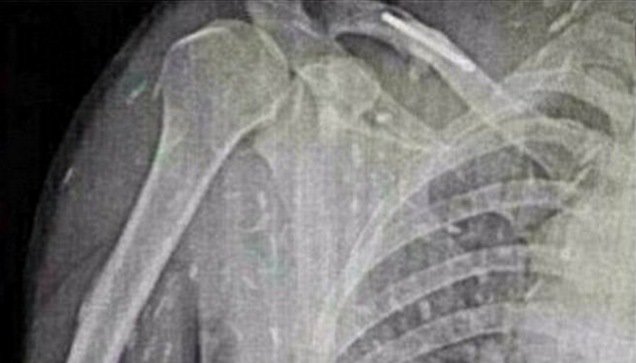

一名平時喜好吃壽司及生魚片的男子,因為連日來皮膚癢又肚子痛,不得已就醫後,醫師一幫他照 X 光片才發現...

這名男子的體內全身上下竟都佈滿了縧蟲。縧蟲是寄生蟲的一種,主要寄居在宿主的腸子中,最長的縧蟲甚至能在宿主體內長至 15公尺。